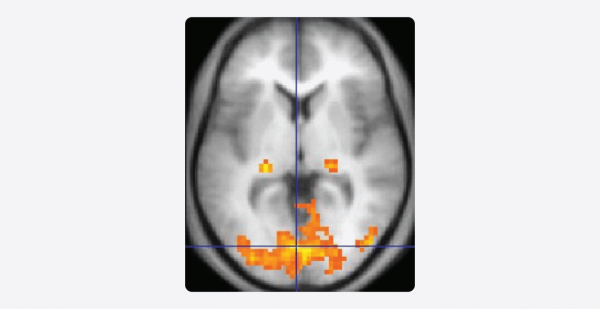

Такой подход был очень полезен на первых этапах, но сегодня концепции, основанные на морфологическом методе, устарели. На смену морфологическому пришли электрофизиологические, электростимуляционные методы, а также наиболее актуальные и предпочтительные методы функциональной нейровизуализации.

К последним относятся фМРТ, диффузионно-тензорная МРТ, позитронно-эмиссионная томография и МЭГ. Все перечисленные исследования неинвазивные, то есть они работают без прямого доступа к мозгу. А еще они позволяют увидеть, какие структуры мозга функционируют в конкретный момент.